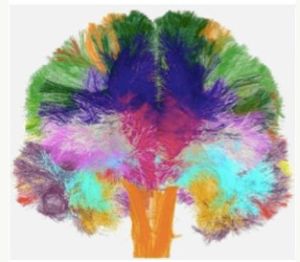

人類腦白質微觀結構圖集 2012年10月,一個由歐洲多個國家研究人員組成的聯合研究小組宣稱,他們利用其開發的新型核磁共振成像技術,歷時三年,完成了人類大腦白質微觀結構圖集。此次聯合研究小組發布的大腦白質圖集涵蓋了100名志願者的腦部三維圖像,詳細描述了大腦白質的微觀特徵,如細胞大小、密度、纖維直徑等。

這些圖像可作為未來醫學和基礎神經科學兩個領域中大腦研究的參考標準,不僅有助於科學家對大腦的理解達到一個新的高度,同樣使得那些非專業用戶,如醫生或醫療人員,可以利用它來了解有關大腦的知識。

該圖集的完成,將大大推動科學家對人類大腦白質的研究,對於未來神經科學和醫學的研究發展具有重要意義。